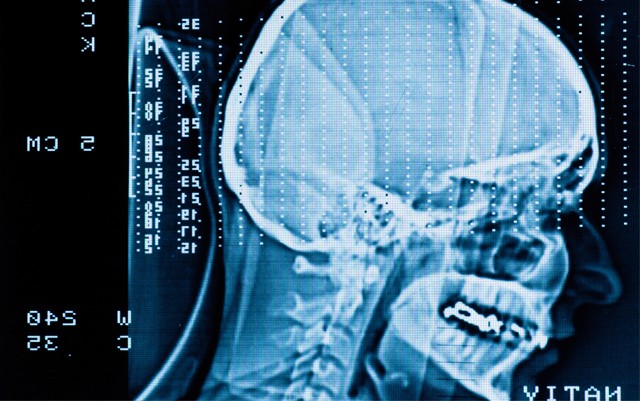

Researchers took rats and, essentially, gave them controlled concussions under anesthesia. These rats were then treated (or not) with ACEA and then tested to see if they could recognize novel objects and find their way out of a water maze. These are standard tests of learning (novel object recognition requires that a rat discerns an object as new) and memory (the fastest way to escape) that can be reliably reproduced in rats. What the researchers found was that rats treated with ACEA demonstrated a vastly-improved ability to discern novel objects from their sham-treated counterparts, and furthermore decreased their time to escape the water maze. Perhaps most interesting of all was that the lesions of both groups were indistinguishable between them.

This indicates that the drug treatment somehow preserves function even in injured neurons. It might not actually prevent the injury from happening, but allow the brain to continue to function despite the injuries, whether these are chemical or traumatic. Another study of ACEA has found that it exerts its effects via the mitochondria by limiting the influx of calcium. This could have profound effects on how doctors manage concussions and brain injuries.